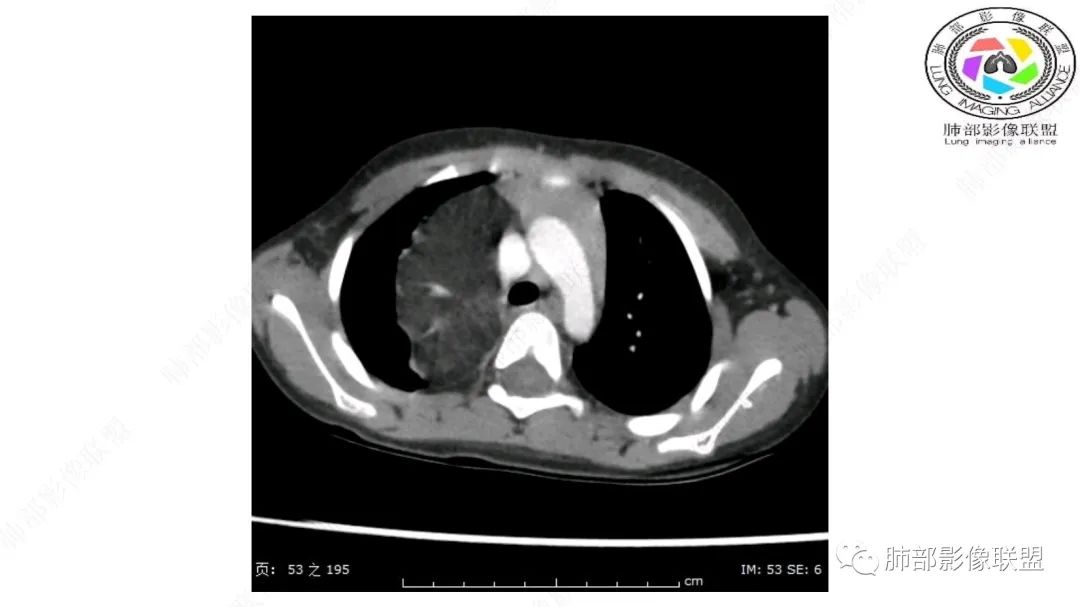

右上纵隔混杂密度肿块,边缘光整,与纵隔分界清,其内多发脂肪密度,增强无明显强化,其内血管穿行,考虑纵隔脂肪母细胞瘤,鉴别畸胎瘤,脂肪肉瘤。

右纵隔团状,密度不均,脂肪密度为主,内可见腺体样组织,类似乳腺,病灶边缘有分叶,与胸腺关系密切,增强后血管穿行。考虑胸腺脂肪瘤(不典型垂乳征),鉴别畸胎瘤。

患儿3岁 咳嗽检查发现纵隔占位。右肺上叶受压表现,占位以脂肪组织密度为主,似见分隔,首先考虑为脂肪母细胞瘤,鉴别脂肪瘤,畸胎瘤。

病灶属于交界区,主体位于肺内,占位效应明显,前方突入胸壁,胸腺受压变形,胸膜显示欠清楚;病灶包绕上叶肺动脉;似乎有体动脉供血。符合肺内的点:包绕上叶肺动脉分支;符合纵隔的点:前方似乎突入胸壁,与胸腺关系比较密切,但是与上腔静脉的关系提示病灶不支持纵隔来源,前纵隔的常规会将上腔静脉受压后移、外移,这是不符合的。

手术记录:见右肺上叶肿物,肿物与右肺上叶关系密切。与纵隔无粘连,逐步分离肿物,见肿物大小约6cm*5cm,边界清楚,于右肺上叶粘连,边界清楚,肿物包绕右肺上叶血管及支气管。超声刀逐步游离肿物,完整切除肿物,右肺上叶肺组织无破溃,表面无出血。

1.右上肺-纵隔交界区巨块影,主体位于右肺一侧,紧贴胸腺、头臂干、右锁骨下动脉、上腔静脉、奇静脉等,不能分离,但病灶整体边界清楚。注意上述相邻腔静脉等结构未见受压变形,纵隔亦未见明显向左推移,至少提示两点:

2.肺动脉穿行也许是肺内来源最重要支持点!